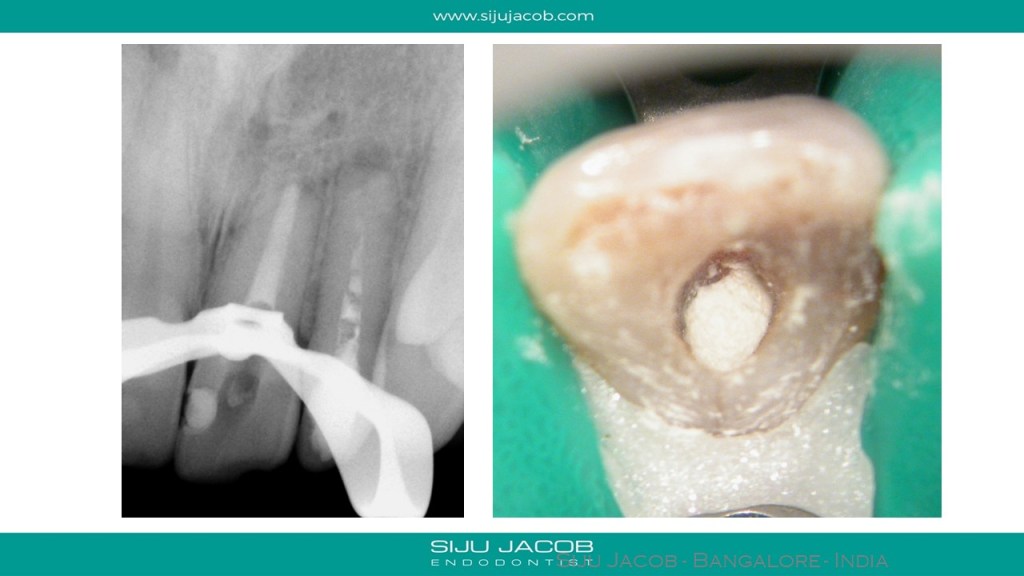

This patient had a history of RCT followed by surgery. While Re-treating, in the lateral incisor, i could get a cone-fit with a #45 master cone. The central however, had an open apex and was inflamed. I placed calcium hydroxide for 2 weeks and packed the central with MTA apically.